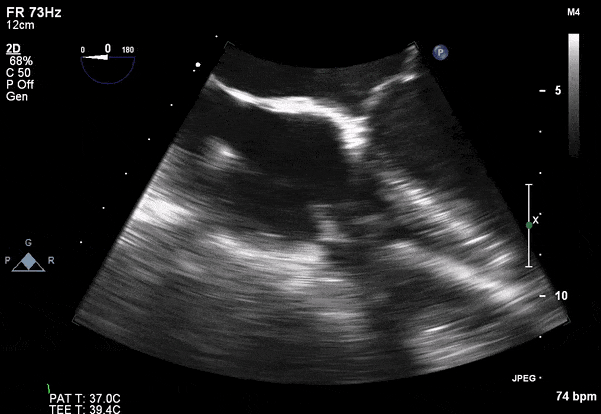

Role of Echocardiography

- Echo plays an important role in the diagnosis of infective endocarditis.

- Helps identify vegetations, new valvular lesions, abscess, and other complications of endocarditis.

- Transthoracic (TTE) should be performed in all cases of suspected infective endocarditis

- Transesophageal (TEE) should be performed if TTE images are inadequate or ongoing suspicion for infective endocarditis.

Transesophageal Images

Case 2 (Pulmonic Valve IE)